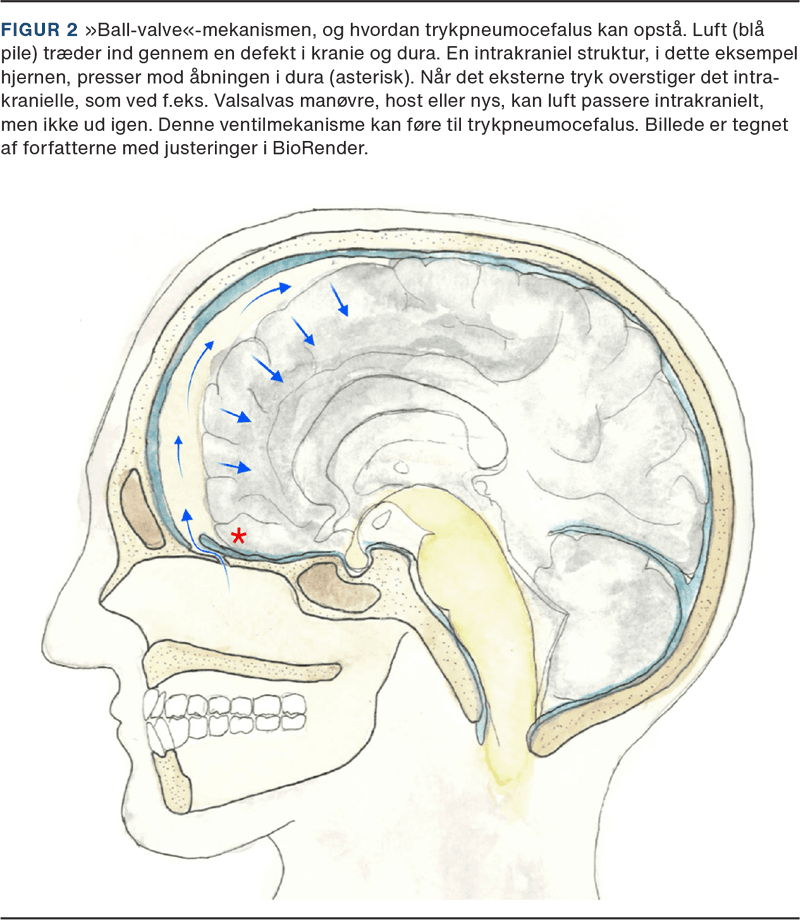

Trykpneumocefalus defineres som intrakraniel luft, der udøver masseeffekt på hjernen og kan medføre forhøjet ICP med dertilhørende symptomer, som inkluderer hovedpine, kvalme/opkastning, motorisk uro, fokale neurologiske udfald, f.eks. kranienervepåvirkning, kramper samt faldende bevidsthedsniveau og ultimativt død [9, 17, 18]. Trykpneumocefalus er beskrevet i forbindelse med mange af de tidligere nævnte ætiologier, herunder efter forskellige neurokirurgiske procedurer, traumer og spontant [9, 17-20]. Mortaliteten for ubehandlet trykpneumocefalus er ukendt, men må antages at være høj [20]. Trykpneumocefalus kan tænkes at opstå både som følge af en ventilmekanisme og som følge af udtalt CSV-lækage som tidligere beskrevet [9]. Et radiologisk fund, som kan ses ved trykpneumocefalus, er Mount Fuji-tegnet, hvor frontallapperne på aksiale CT eller MR-snit fremstår spidse, sammenpressede og adskilte ved frontalpolen, hvilket giver et udseende, der minder om den kendte bjergsilhuet (Figur 3). Det er dog vigtigt at pointere, at både sensitivitet og specificitet er relativt lav, så ikke alle patienter med trykpneumocefalus udviser dette tegn, og at ikke alle patienter med Mount Fuji-tegn har trykpneumocefalus [20].